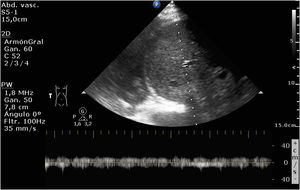

Varón de 86 años ingresado en UCI por insuficiencia cardíaca derecha (ICD) secundaria a comunicación interauricular tras implante de Mitraclip®, hipertensión pulmonar crónica grave, fracaso renal agudo y elevación de transaminasas y bilirrubina. Se realizó VExUS (Venous Excess Ultrasound Score). La figura 1 muestra la inversión del flujo durante la sístole ventricular en el doppler de venas suprahepáticas (flecha roja). La figura 2, el patrón venoso interlobar renal monofásico (ausencia de flujo venoso [flechas azules] en la sístole [flechas blancas]). Ambos hallazgos son sugestivos de congestión venosa sistémica (CVS) grave. Sin embargo, el doppler de vena porta (DVP) (fig. 3) no fue pulsátil (como se esperaría en la CVS). La fibrosis portal por cirrosis (secundaria a ICD) impide la transmisión de pulsatilidad en el flujo venoso, siendo el DVP, en este caso, no valorable dentro del VExUS para el diagnóstico de CVS, por tratarse de un resultado falso negativo.